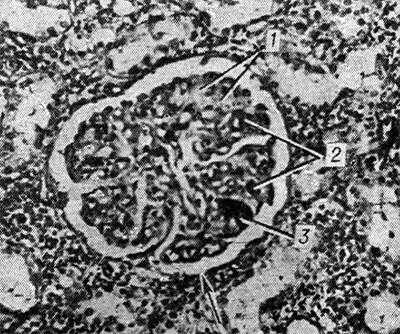

Рис. 1. Микропрепарат почки при болезни Мошкович: стрелкой указано фибриноидное набухание и плазматическое пропитывание стенки мелкой артерии; окраска гематоксилин-эозином, х 200.

Рис. 2. Микропрепарат почки при болезни Мошкович: почечный клубочек (указан стрелкой) с участками фибриноидного некроза (1), окклюзией просветов капиллярных петель (2) эозинофильными массами и скоплением гематоксилинофильных ложноизвестковых зерен (3); окраска гематоксилин-эозином, X 200.

Микроскопически во всех органах обнаруживают характерное поражение капилляров, артериол и мелких артерий, к-рое наиболее выражено в почках и зависит от длительности течения заболевания. При кратковременном течении (до 1 месяца) и обострении процесса преобладают фибриноидное набухание с плазматическим пропитыванием (рис. 1) с последующим фибриноидным некрозом сосудов и окклюзией просвета эозинофильными PAS-положительными массами, дающими положительную реакцию на фибрин. При длительности заболевания более 2 мес. наряду с фибриноидными изменениями выражены пролиферативные и склеротические. Гематоксилинофильные зернистые массы в сосудах, дающие отрицательную реакцию Коссы на известь и названные Прокшом и Томси (P. Proks, F. Tomsi, 1955) ложноизвестковыми зернами, могут быть скоплением микробов или продуктами гемолиза. Они часто встречаются в капиллярах почечных клубочков наряду с фибриноидным некрозом капиллярных петель и окклюзией их эозинофильными массами (рис, 2). В печени, почках, селезенке, костном мозге, лимф, узлах с помощью реакции Перльса обнаруживают скопления гемосидерина. В костном мозге и селезенке количество плазматических клеток увеличено.